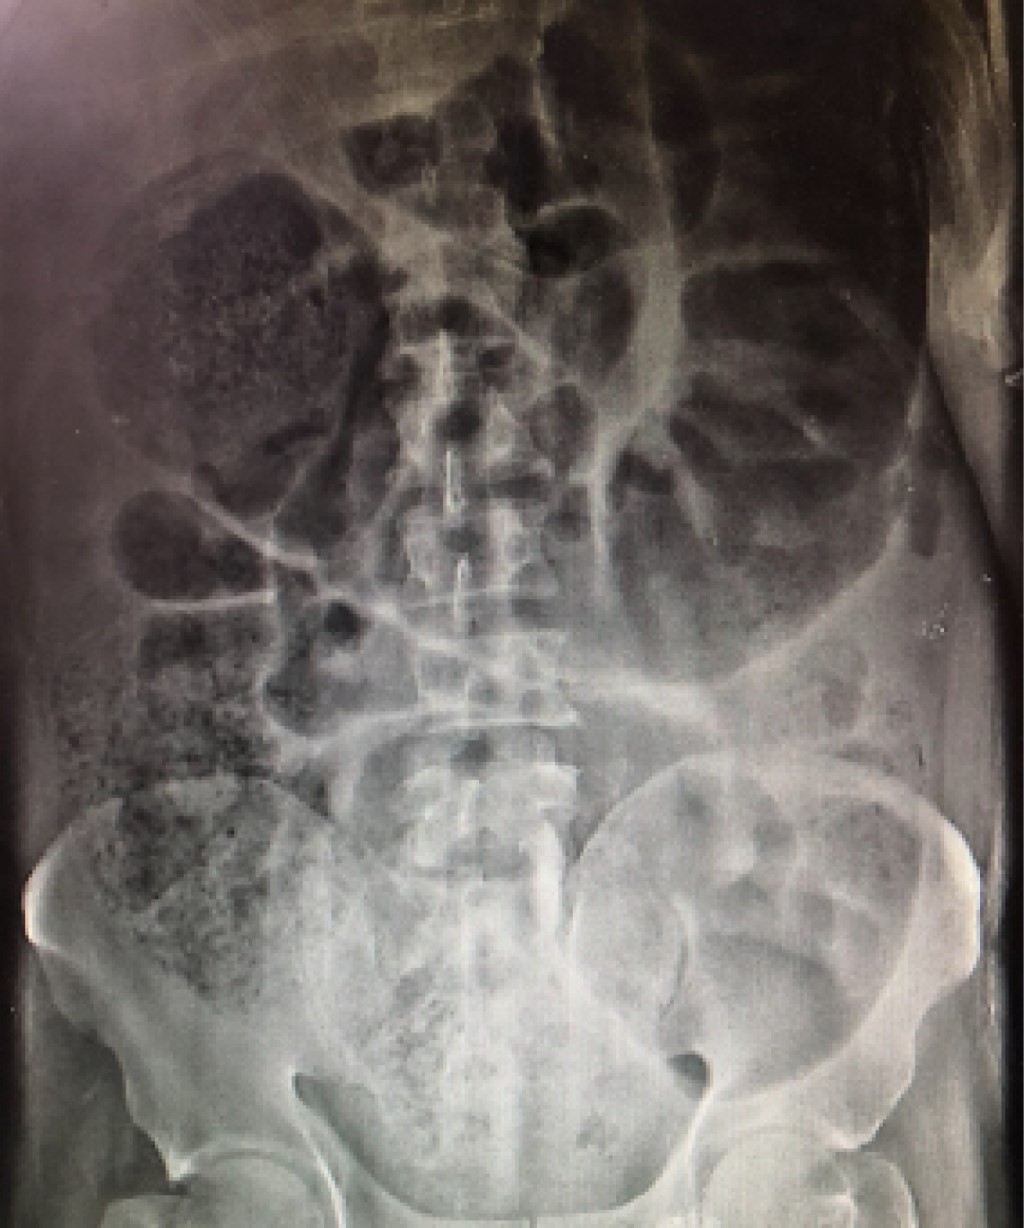

Figure 2